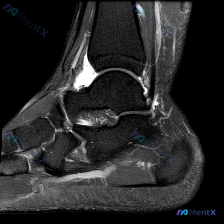

刚看到这份踝关节MRI的读片资料,整理一下病例和完整分析思路,这个病例的鉴别点其实挺典型的,分享给大家。 基本影像信息 这是一张踝关节MRI冠状位T2加权图像,针对影像的观察结果整理如下: 1. 骨性结构:胫骨、腓骨远端及距骨形态基本正常,骨髓信号无明显异常,没有急性骨挫伤、骨髓水肿,也没有明显游离...

刚整理完一份踝关节MRI的读片分析,关于软组织积液的鉴别思路挺典型,分享给大家一起讨论。 病例影像基本信息 这是一份踝关节MRI T2序列轴位影像,扫描层面为距骨体水平,显示踝关节及周围软组织结构: 1. 骨骼表现:距骨及周围骨性结构骨皮质完整,骨髓信号无局灶异常高信号,排除明显骨挫伤、骨折或骨髓水...

看到这份踝关节MRI读片资料,整理出来和大家分享分析思路。 病例基本影像信息 这是踝关节MRI轴位T2加权图像,先给大家梳理影像上的基本发现: 1. 骨骼结构:距骨、外踝(腓骨远端)、内踝(胫骨远端后部)骨皮质连续,无骨折或骨质破坏,骨髓信号均匀,无异常骨髓水肿 2. 肌腱与韧带:腓骨长/短肌腱、跟...